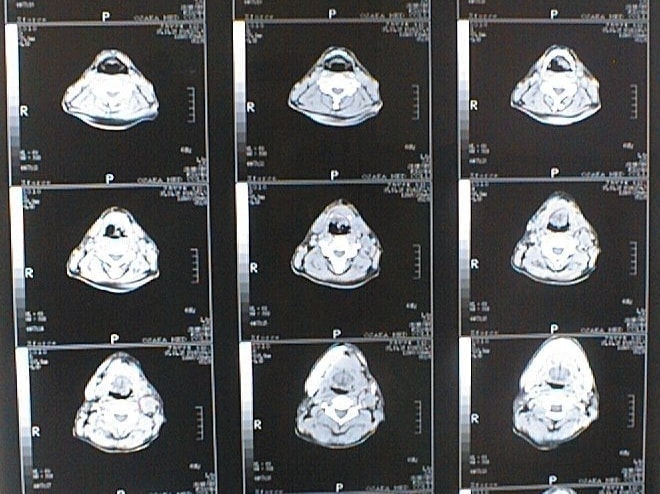

末期がん宣告時と末期がん消滅時の診断画像比較

ここでは、末期がんと宣告された時のCT&MRI画像と、その約3か月後の末期がん消滅時の画像を比較して頂けます。(写真左が「末期がん宣告時の画像」、写真右が「末期がん消滅後の画像」)

MRI画像比較

中咽頭末期がんMRI画像②

入院当時MRI画像②

中咽頭末期がん消滅時MRI画像②

入院3か月後癌消滅MRI画像②

中咽頭末期がんMRI画像③

入院当時MRI画像③

中咽頭末期がん消滅時MRI画像③

入院3か月後癌消滅MRI画像③